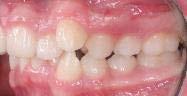

En las fotografías intraorales (Figura 3) observamos una clase II molar bilateral, clase II canina derecha, clase III canina izquierda, apiñamiento severo superior y moderado inferior, presencia de mordida abierta anterior y posterior a nivel de premolares (Figura 4), forma de arco triangular en la arcada superior y forma de arco oval en inferior, ausencia del OD 46 y presencia de un diente supernumerario.

Figura 2. Fotografías extraorales frente y perfil. Figura 3. Fotografías de frente, lateral derecha, lateral izquierda.